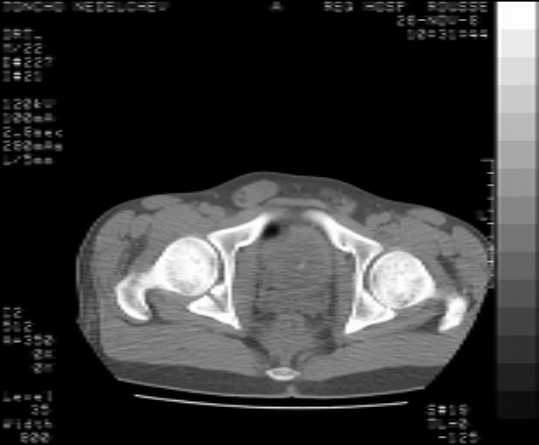

The details of the fracture are not so clear from the images sent...would you be able to send along an AP and Judet images as well as some additional axial images above and below the joint?

I’m not so sure that your patient has a Tr+PW pattern based on the images sent...maybe the fracture’s exact name won’t matter in the long run, but it’d be great to see enough images to make an accurate comment.

Without complete CT images and/or oblique radiographs, it's difficult to answer your question definitively, but it appears that there may not be a posterior wall fracture that requires a posterior approach. A successful reduction through an ilio-inguinal approach will have a faster recovery, and not risk SGN injury or heterotopic ossification.

Here are some more axial images. What is your opinion as for the timing of the operative treatment?